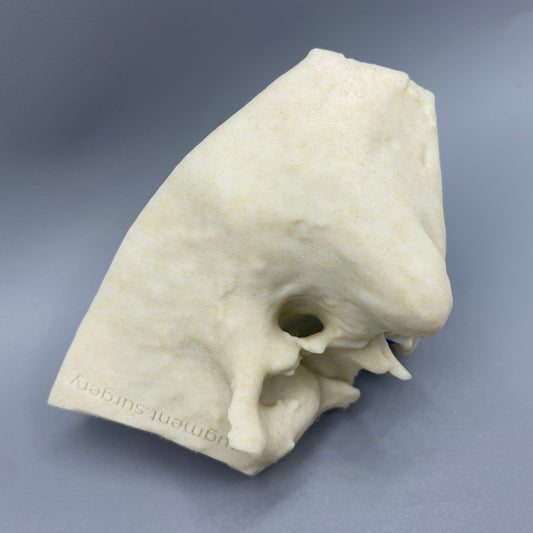

Plant-based surgical simulators made in the U.S.A.

Dissect each one to learn human temporal bone anatomy, hearing and vestibular systems.

Customize anatomy, colors, quantities, and more by contacting michelle@augment.surgery